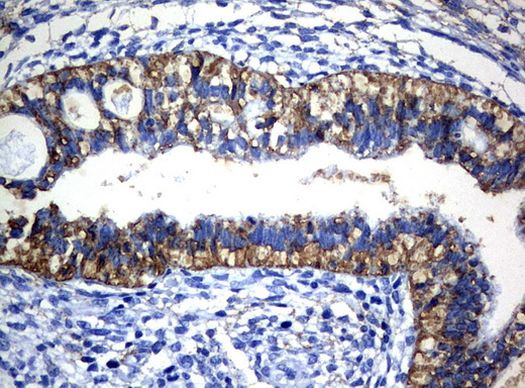

CTAG1B Antibody in Immunohistochemistry (Paraffin) (IHC (P))

CTAG1B Antibody (UM500060) in IHC (P)

Immunohistochemical staining of paraffin-embedded human testicular cancer tissue using anti-CTAG1B mouse monoclonal antibody. (UM500060; heat-induced epitope retrieval by 10mM citric buffer, pH6.0, 120°C for 3min) {{ $ctrl.currentElement.advancedVerification.fullName }} 验证信息 View more